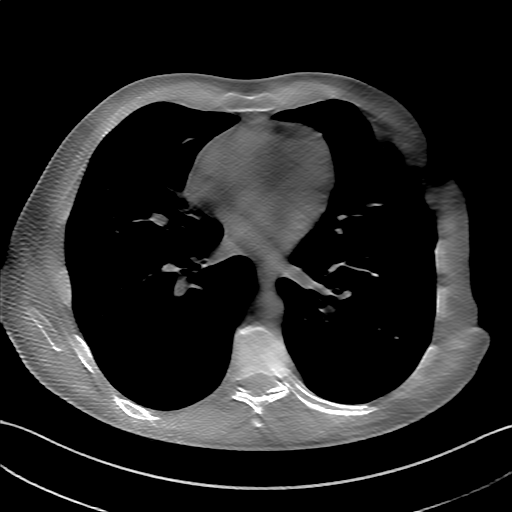

GT

FBP

HQS-CG

DuDoNet

Meta

Meta_re

EPNet

Qualitative Results Comparison. We also visualize the reconstruction results of these methods on AAPM-test and COVID-test datasets. As in the first three rows of Fig. 4, the reconstructed images from ours and retrained MetaInvNet show the best visualization quality on AAPM-test set across different angle numbers. Besides, our results show sharper details with the additional utilization of in the projection domain. When testing the reconstructed image on the COVID-test set, our result also gives sharper details but with more artifacts since the data distribution is very different. Although HQS-CG has achieved better quantitative results on the COVID-test dataset, the reconstructed image of their model in the fourth row is even smoother than FBP.